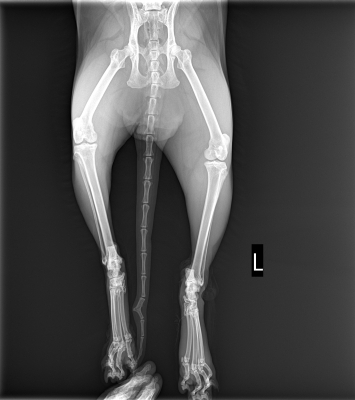

私は腰周りの骨折も心配だったので、先生に頼んで全身のレントゲンをお願いしました。

そして、レントゲンの結果、チャトラの脚は骨折していなかったことが分かったのです。

先生の見立てでも骨折っぽい歩き方だったそうですが、幸いにも脚や腰周りに骨折した部分はありませんでした。

ただ、ケガはかなり深い様子だったため、1針縫合して治療することになりました。